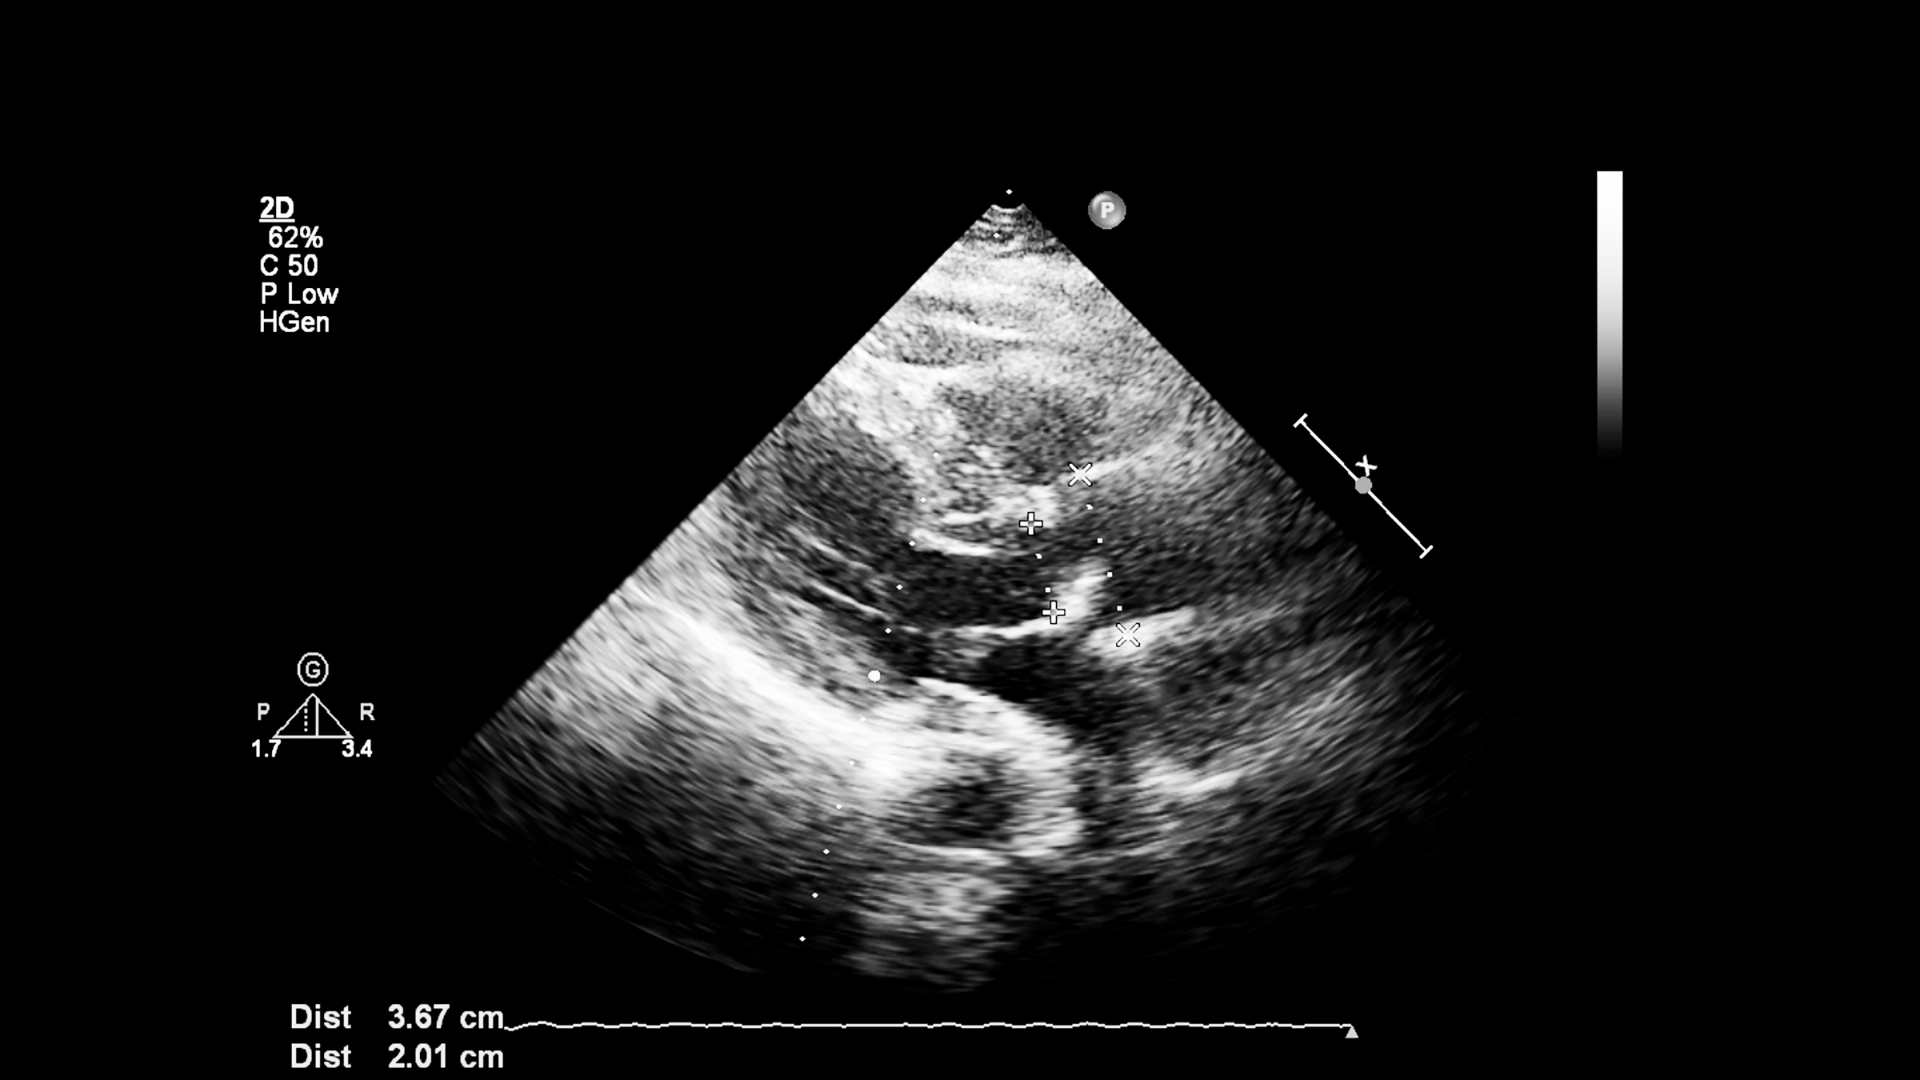

Bên cạnh siêu âm thông thường, nhiều người quan tâm đến siêu âm đàn hồi gan. Đây là phương pháp hỗ trợ đánh giá độ xơ hóa của gan và thường được chỉ định trong một số trường hợp cụ thể.

Chi phí siêu âm đàn hồi gan thường cao hơn so với siêu âm thông thường. Mức giá có thể dao động ở mức trung bình cao hơn, tùy vào cơ sở và thiết bị sử dụng.

- Công nghệ chuyên sâu hơn.

- Thiết bị hiện đại hơn.

- Thời gian thực hiện và phân tích kỹ hơn.